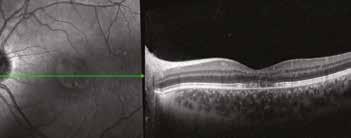

Milano nel 2017. Nel maggio del 2023 inoltre, sempre al medesimo congresso, il Dottor Alfredo Pece mi ha nuovamente invitato a mostrare un caso analogo, ma ancora più esemplificativo, in quanto ottenuto in un giovanissimo paziente affetto da Maculopatia vitelliforme giovanile di Best, in cui i primi 5 aa di assenza di terapia mostravano un significativo peggioramento visivo da 10/10 bilaterale a 6-7/10 in OD e 7/10 in OS con iniziale comparsa di metamorfopsie e segni di iniziale sofferenza neuro-recettoriale. Nel follow-up successivo all’introduzione di DHA al-

gale (OMEGAL DHA capsule softgel) con aggiunta di un complesso antiossidante contenente curcuma MERIVA ®, luteina, zeaxantina, vitamine c, e, d3, rame e zinco si osservava un’eclatante risposta progressiva nei successivi 18 mesi in OS e 24 mesi in OD in termini di completo riassorbimento dell’accumulo lipofuscinico maculare, notoriamente tossico per l’EPR, senza significativa evoluzione atrofica e miglioramento significativo delle linee IS-OS recettoriali in entrambi gli occhi e della qualità visiva e QoL del paziente con BCVA finale di 9/10 in OD e 9-10/10 in OS.

Il lungo follow up del paziente durato 5 anni in assenza di cura integrativa continuativa se non saltuario uso di formula ared2 per brevi cicli mostra un significativo peggioramento anatomico strumentale OCT e funzionale del paziente con evoluzione dallo stadio 1 allo stadio II/III e solo dopo uso concomitante di DHA algale OMEGAL DHA ed un Complesso antiox si osservava una eclatante ed imprevedibile risposta, nei successivi 18 mesi in occhio sinistro e 24 mesi in OD, con completo riassorbimento del voluminoso accumulo lipofuscinico senza significativa evoluzione atrofica. Dopo inizio della cura invece si osserva un miglioramento significativo e duraturo dell’aspetto delle linee recettoriali e conseguentemente della qualità visiva in entrambi gli occhi, con un significativo miglioramento della qualità di vita del giovane paziente.

Sopra, miglioramento progressivo dopo cura.